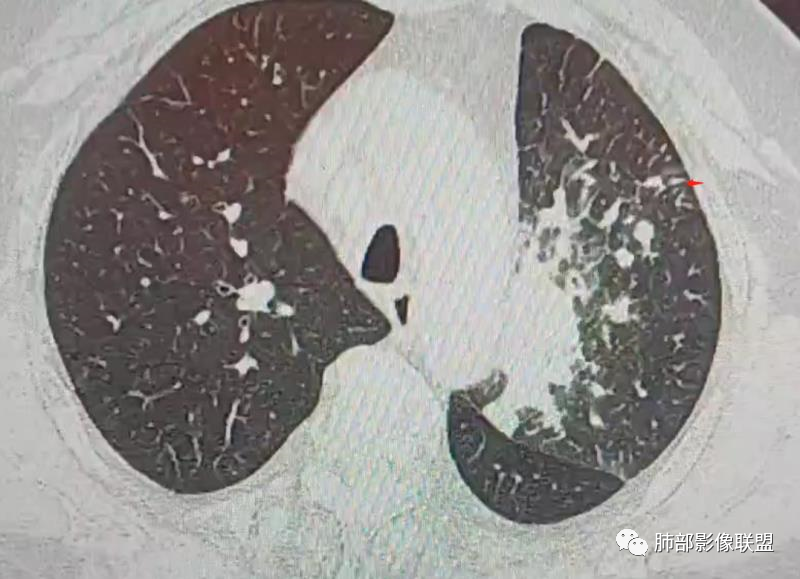

三、影像表现:左肺上叶多发片状高密度影,散在,边缘模糊,支气管壁稍增厚,中轴间质、小叶间隔增厚、有结节感,左肺上叶前段病灶可见胸膜增厚,部分小支气管不能分辨;右肺上叶后段混合磨玻璃结节,边界清,邻近胸膜凹陷;纵膈淋巴结肿大;心包增厚;左侧少量胸水。此外,扫及右侧胸腔内甲状腺肿;左侧肩胛骨旁肌群内脂肪瘤。

四、综合分析:老年男性,以咳嗽咳痰为主要临床表现,无发热,白细胞正常,影像表现为左肺上叶片影,前段结节影、胸膜增厚、部分小支气管不能分辨。左肺上叶中轴间质增厚、小叶间隔增厚、结节感,肺门纵隔见肿大淋巴结,尽管肺部病病灶边缘特征不典型,但高度疑及癌性淋巴管炎这一“次生灾害”却具有相当重要提示意义,而肺癌中最常伴癌淋的就包括腺癌。右肺上叶后段混合磨玻璃结节,边界清楚,张力明显,具有一定特征性,高度指向浸润性腺癌。这对于左肺病灶具有一定程度“助攻”效应。总体而言,本例左肺病灶的诊断关键点在于判断出癌性淋巴管炎。癌性淋巴管炎的结节在外围间质多见,小叶间隔可呈串珠状、结节状增厚,由于出血及水肿,小叶间隔增厚较明显,或呈不规则增厚。有的肺小叶呈多角状阵列。常合并胸水。

PLC的主要CT征像当中肺纹理异常改变最常见,肺纹理不规则增多、增粗并多发微小结节状更形象解释癌细胞在淋巴管内生长成结节及周围间质增生,导致淋巴管通道堵塞,远处淋巴液回流受阻,通过其它细小交通回流,从而导致肺纹理增粗增多,是PLC较有特征性CT征象,其它疾病所导致的肺纹理增多增粗一般较规则,可为粗细不均或受牵拉变形却极少出现结节状增粗并呈串珠状排列。小叶间隔不规则增厚并多发小结节也是因为小叶间隔淋巴管癌细胞生长及淋巴管通道受阻扩张所致,虽然小叶间隔结节状增粗,但小叶结构不变形是PLC较为特征的CT表现,肺纤维化、 肺水肿、肺胶原病及结节病等肺间质性病变中较少见小叶间隔结节状增粗,而且它们一般导致肺小叶结构变形。肺小叶内间质增生及(或)核心小结节无明显特异性,其表现与特发性肺纤维化、 尘肺及结缔组织病及其它可导致肺间质性纤维化疾病的小叶内间质增厚相类似。PLC导致的胸膜增厚也有一定特征,一般累及胸膜范围较广,程度轻,密度较淡, 部分呈花边样改变,以叶间胸膜较常见,绝大部分病例叶间胸膜受累呈轻度增厚并沿表面排列多发微小结节,伴随PLC其它征象,未见单独存在。肺内结节及 (或)小斑片状实变影无特异性, 与肺结核、炎症、肺血行转移瘤及类风湿等结缔组织病的肺部表现相似,也可能为合并血行转移及肺部感染。纵膈及肺门淋巴结肿大、胸腔及心包积液均无特异性,曾有文献报道,单侧叶间裂积液对PLC的诊断有相对特异性, 因单侧的叶间裂积液主要是由于胸膜下淋巴管堵塞,淋巴回流受 阻所致,可提示PLC的存在。

图1、2为同一病例,左肺下叶背段周围型肺Ca并左肺下叶局限型PLC,肿块与左下肺门间肺纹理不规则增粗,肿块与膈面有串珠样高密度影相连。图3为乳腺癌化疗后多发转移并弥漫型PLC,双肺多肺叶肺纹理不规则增粗增多并多发微小结节,其中右肺上叶后段肺纹理多呈典型的“毛刷征”,双肺上叶胸膜下区可见多发垂直于胸膜的不规则增厚的小叶间隔及微小结节。图4为右肺上叶周围型肺癌并弥漫型PLC,左肺上叶背段肺纹理不规则增粗增多呈典型的“毛刷征”,右侧叶间胸膜轻度增厚及多发微小结节。图5为胰腺癌术后多发转移并弥漫型PLC,双肺广泛肺纹理增多增粗并多发微小结节,双肺胸膜下多发肺小叶间隔增厚并见微小结节;图6(MPR冠状位)为食管癌术后肺弥漫型PLC,左肺广泛肺纹理不规则增多、增粗及多发小结节,边缘模糊。